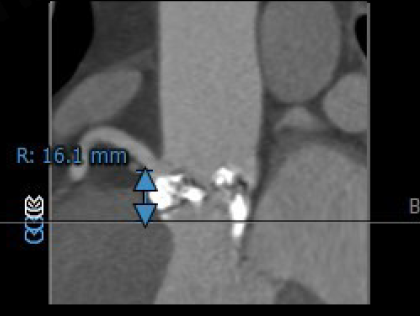

左冠开口高度:16.1mm

右冠开口高度:16.1mm